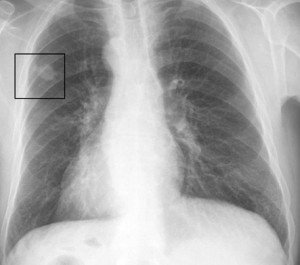

Şəkil

Rentgen, KT, MRT, biopsiya diaqnostikada faydalıdır.

Əsas müalicəsi radikal rezeksiyadır. Bəd xassəli plevral eksudatın olması radikal müalicəyə əks göstərişdir. Sarkomaların radikal müalicəsindən sonra 5 illik yaşama 16,8% təşkil edir. Cərrahi müalicə, şüa və kimya terapiya törəmənin histoloji quruluşundan asılı olaraq tətbiq olunur. Yaranmış defektlər dəri-əzələ loskutu və ya sintetik materialla bərpa edilir.